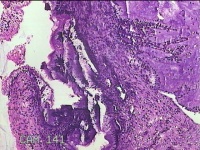

宫颈组织

性别

女

年龄

31岁

临床诊断

宫颈上皮内瘤变

一般病史

发现宫颈CIN2 2个月。

标本名称

大体所见

灰白暗红色组织2.8x1.8x0.3cm一块,表面糜烂,切面灰白暗红色,质软。

所提供图片不具有诊断价值。